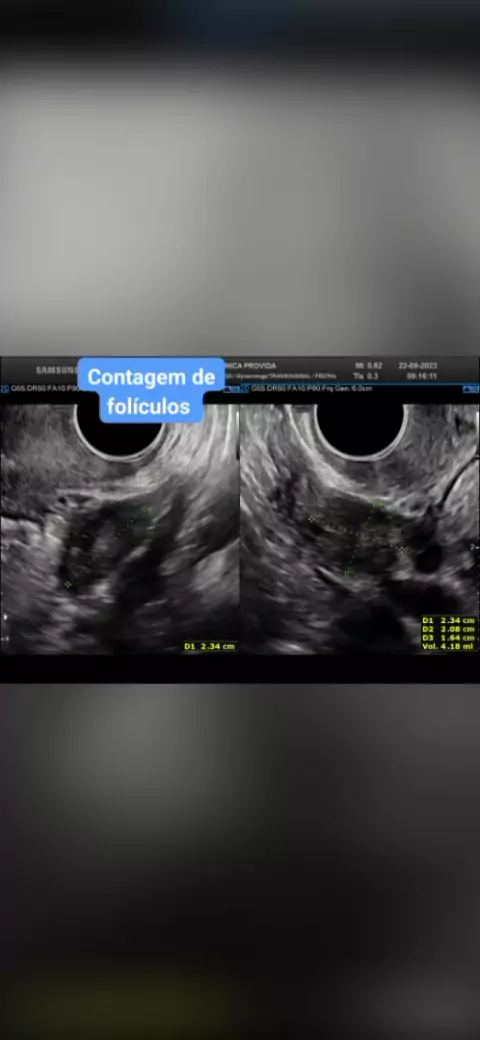

Ultrassom para contagem de folículos; #Brevemamae #pregestante